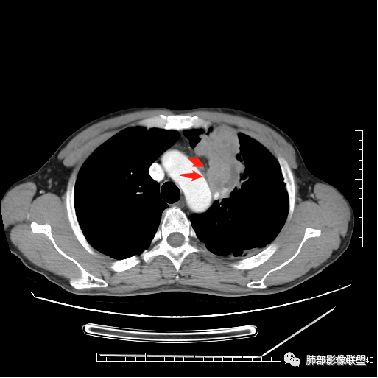

4.病灶整体轻中度强化,强化较均匀,局部见多个管状低密度影,边界清,考虑支气管粘液栓;病灶局部可小灶样的低密度区,未见强化,考虑坏死灶,坏死灶周围见明显强化的壁,壁清楚、光整,未见中断,倾向炎性肉芽肿的坏死;

5.病灶内血管部分走形自然,部分走形僵直、粗细不均,提示病灶有部分破坏力,但是不强;

3.病灶内多支支气管粘液栓,炎性及恶性均可,但是炎性多于恶性;强化杂乱不均,病灶内小灶坏死比规则,支持炎性肉芽肿病变。

鳞癌病灶如较大,强化常不够显著且多见相对大范围湖泊样坏死。